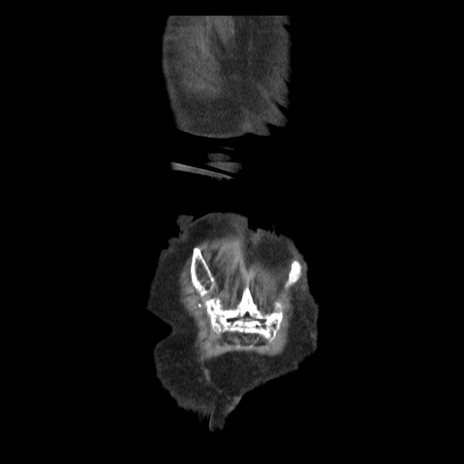

横断像